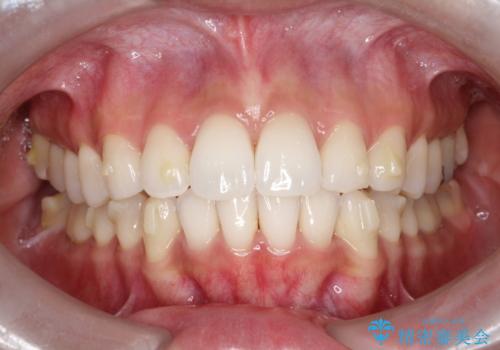

【インビザライン】前歯の凸凹をIPRで改善

- 前歯の凸凹を主訴に来院されました。

前歯を並べるために歯と歯の間にヤスリを入れてわずかに歯を削ることでスペースを確保しています。

歯と歯の間にヤスリを入れてわずかに歯を削ることでスペースを確保する処置をIPRと呼びます。

当院では拡大鏡を用いて丁寧に処置することで歯冠形態を損なわずに行うことができます。